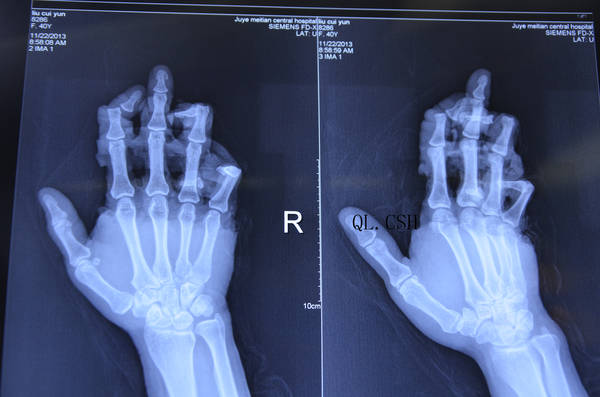

手部滚胶机挤伤,急诊修复。

对于这个病例,动脉移植选择用足背静脉弓,虽然近端接了1、2、3指总动脉,但是远端并没有看到接了同样多的吻合口,近端的吻合口虽然多,但是血管张力不足,同时存在迂曲,很难保证远端的动力,容易发生栓塞,这是血管吻合的一个原则问题(要保证血管适当的张力);静脉也是一样,我们虽然也经常做X形、Y形的血管移植,但是都会给血管适当的张力,而楼主的病例,移植的血管路径太长,几乎都是横行摆放,回流的静脉血几乎不能把血管充盈起来,也是容易栓塞达不到回流效果的。

这种皮肤软组织在指根部撕脱,而指骨、肌腱及远端皮肤软组织完整的病例我见过一些,很多入院的时候就看到指体是有毛细血管反应的,虽然他们的动、静脉血供系统已经破坏。但是骨膜和腱膜上的小动脉甚至指背动脉一样可以提供一部分供血及回流,如果手指的皮肤软组织完整,远端的指动脉穿支更容易向远端提供血供。这个我可能也不好解释原因,我只是说不接血管,指体不一定会坏死,不会坏死也不是说会成活的很好,对于这例患者是一定要接动、静脉的,而且血管缺损也必须移植,我只是质疑这种血管移植方式的效果和直接切取一段段的血管的效果,那种更可靠?对于手掌和手背部皮肤软组织撕脱,不接静脉撕脱的皮肤容易坏死,这个是因为静脉血内淤积了大量的排泄产物,回流不畅胀死的缘故吧

1、吻合口掌侧近4远6,背侧近2远6。掌侧吻合了尺动脉远端、尺动脉的肌肉分支、桡动脉剪断后的两个头(远端的血管口其实应该算是逆行的,但为了手成活,能找到的血管都接上)。

背侧示中指,中环指,环小指分别两根,近端头静脉和贵要静脉断端。因为照片不清,让斑竹误会,首先道歉。不过,大半夜的人困马乏,能有这样照片我已经很满足了,非常感谢台下照相的兄弟,也要感谢我自己,有些照片在喊不着人的时候自己带手套照的。

3、术前手指针刺没有出血,这点相当肯定。这个手的脱套伤还是蛮重的,比你看到的要重很多,清创时确实发现已经脱套到远指间关节了。因为有神经不想过分牵拉,所以没能显露出来。从X光片就能看到,示环小指的远节指骨是脱位的,相当于单指脱套伤,这样的脱套伤你说靠不知名动脉能成活,我还是不敢想象的。这么重的伤,血管又不能外露松解,你想当时就让它通血良好,我觉的还是不现实的。中指吻合尺侧动脉后无通血,后来探查发现远端还有一个断裂口,又重新进行了吻合,接着又吻合了桡侧的动脉,手术中的艰难你是看不到。照片中环小指的的血运稍差,但吻合口处是通血良好的。这样的供血你让静脉完全充盈也是有难度的。下台10多个小时后,中环小指才红润。